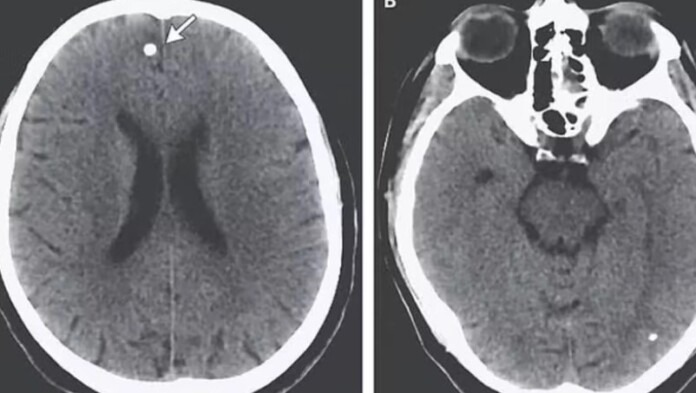

Um caso preocupante envolve uma jovem de 21 anos, identificada como T.E., que adquiriu os comprimidos por redes sociais. Após iniciar o uso, ela perdeu peso, mas começou a sofrer cólicas severas e notar substâncias estranhas em suas fezes. Inicialmente, achou que eliminava gordura, mas os sintomas pioraram com o tempo, culminando em dores de cabeça extremas e momentos de amnésia. No hospital, após exames e confissão de que ingeriu ovos de tênia, os médicos descobriram múltiplas lesões cerebrais causadas por duas espécies do parasita: Taenia saginata e Taenia solium.

A infestação no cérebro levou três semanas de tratamento intensivo, com uso de esteroides e antiparasitários. Após seis meses, T.E. se recuperou totalmente, e sua história agora serve de alerta para os riscos dessa prática perigosa.